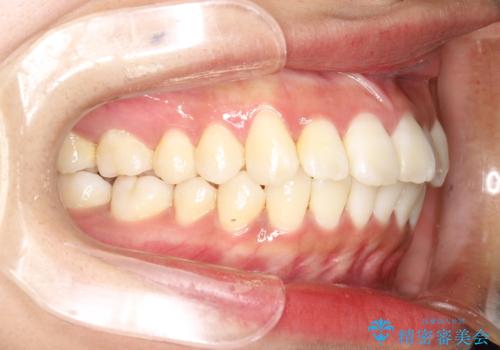

がたがたをインビザラインで整った歯並びへ

- 全体的ながたつきを主訴に来院されました。

抜歯矯正も考えられる状態でしたが、患者様が非抜歯での矯正を希望されたため、歯と歯の間をわずかに削りスペースを作り、全体を整える計画としました。

非常に協力的な患者様でしたので、スムーズに治療を終えることができました。